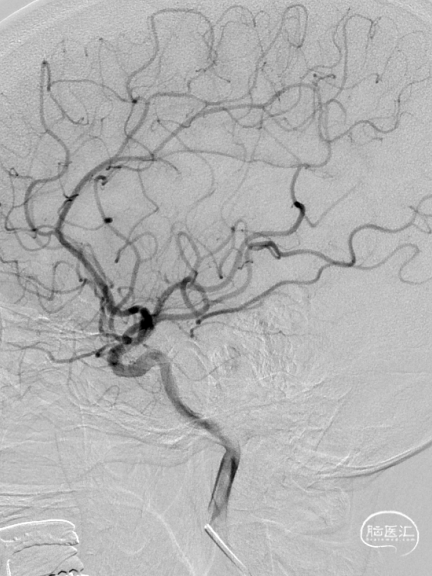

术前影像资料